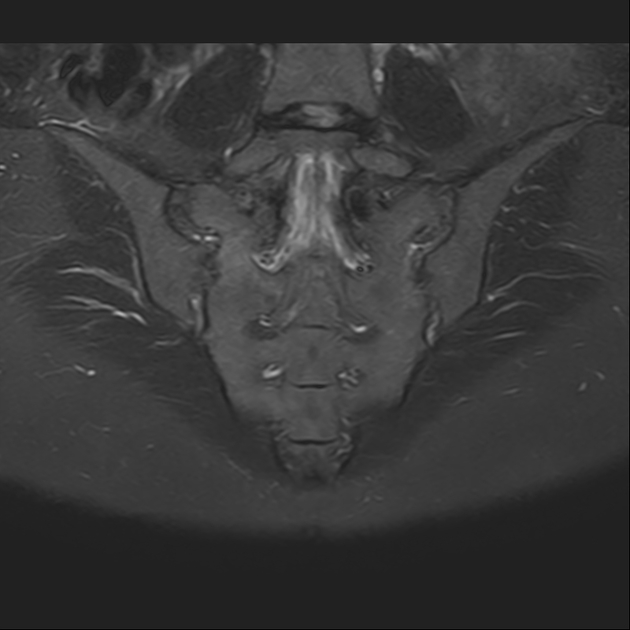

磁共振检查:

STIR

6、磁共振上可以发现骨折线周边明显的骨髓水肿,增强扫描明显强化

磁共振影像表现